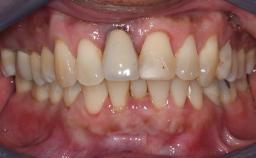

The patient presented with a failing tooth-supported fixed dental prosthesis with cantilever extension replacing the right maxillary central incisor. His chief presenting complaint was poor esthetics, in particular the dark discolored margin around the abutment tooth, the maxillary left central incisor. He reported a history of trauma at a young age, which necessitated the replacement of his maxillary right central incisor as well as root canal therapy of the adjacent left central incisor. The existing prosthesis had been in situ for over 20 years. The initial periapical radiograph displayed good proximal bone levels at the adjacent teeth and a wide incisive canal, which was a concern. The left central incisor presented a very wide root canal treatment with compromised radicular dentin thickness, which was a consideration in the decision between a new tooth-supported fixed dental prosthesis vs. an implant-supported prosthesis. After a lengthy discussion on the risks and benefits of both treatment options, the patient decided on a single-tooth implant replacement.

Patient's Esthetic Expectations Low Medium High

Lip Line No exposure of papillae Exposure of papillae Full exposure of mucosa margin